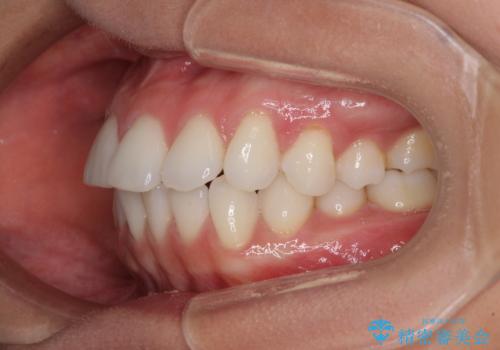

【モニター】インビザラインで口を閉じやすく

- 前に出ている上顎前歯が気になるとのことで来院された患者様です。

インビザラインを用い、IPR(歯と歯の間を削る)と歯列全体を後方に移動させることで、可能な限り前歯の突出感を改善することとしました。

元々の歯列も整っており、横顔の印象の出っ歯ではなかったため、仕上がりに満足できない可能性があると心配しておりましたが、口が閉じやすくなり、患者様には大変満足していただきました。